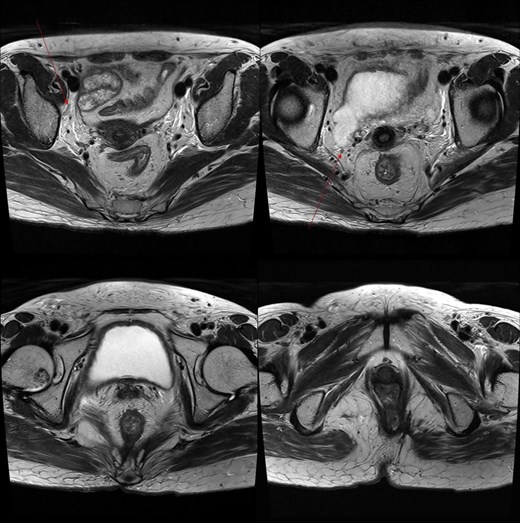

Marked reduction in the size of the tumor and lymph nodes following CCRT.